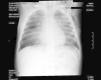

El primer día de ingreso persiste febril e inicia tos. La serología de sarampión (IgM e IgG) es dudosa; el resto, negativo. Se comunica la sospecha de sarampión a Salud Pública y se extraen muestras de orina, sangre y exudado orofaríngeo para estudio mediante reacción en cadena de la polimerasa (PCR). Se solicita pro-BNP por la sospecha inicial de EK, cuyo resultado fue < 50 pg/ml (no significativo). Al día siguiente, inicia tiraje subcostal, taquipnea (50rpm) y SatO2 < 94%, hasta entonces normal. Auscultación con espiración alargada sin ruidos patológicos. Radiografía de tórax: atrapamiento aéreo, sin otros hallazgos. Se inicia oxigenoterapia y antibioterapia con cefotaxima. Empeoramiento 24 h después, con taquicardia, aleteo nasal, frecuencia respiratoria 60rpm e hipoventilación con subcrepitantes finos en ambas bases pulmonares. Nueva radiografía de tórax: infiltrado perihiliar intersticial, compatible con neumonía sarampionosa o edema pulmonar, y enfisema subcutáneo axilar izquierdo (fig. 2). Ecocardiografía normal. Se añade cloxacilina y clindamicina, se solicita nueva serología para sarampión y se traslada a UCIP de nuestro hospital de referencia, donde permanece 6 días. Precisa ventilación mecánica no invasiva durante 72 h, drenaje torácico por neumotórax derecho, furosemida y fármacos vasoactivos. Desarrolla un cuadro compatible con síndrome de dificultad respiratoria aguda moderado, según la escala de Murray10. La segunda serología tampoco es concluyente. La PCR para sarampión es positiva en las tres muestras recogidas. Evolución clínica satisfactoria, con mejoría del cuadro respiratorio y descamación generalizada. La madre refiere haber pasado la enfermedad en su infancia. No se describen otros casos intrafamiliares. Posteriormente, se confirman, mediante serología y PCR, otros 2 casos no complicados en la escuela infantil de la menor.